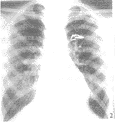

例2,X线胸片:两肺血轻多,主动脉结宽,肺动脉段平,其左上纵隔旁隐约可见斜行带状高密度影(见图2),心脏不大,心胸比率0.48。心电图:右心室肥厚。超声心动图:右房、室内径增大,左心内径正常,声学造影诊断为肺动-静脉瘘。CT增强扫描示主动脉弓旁可见一异常血管断面。右心导管检查:上腔静脉血氧饱和度比右无名静脉高12%,QP/QS=1.4。主肺及左肺动脉造影:右上、下及左下肺静脉分别回流入左房,左上肺静脉经垂直静脉、左无名静脉回流至右上腔静脉(见图3、4),房、室水平未见左向右分流。该例行左上肺静脉与左心耳吻合术。

X线胸片的表现取决于左向右分流量的大小,单纯的左上肺静脉畸形引流常为少量分流,肺血轻度增多,一般不引起心脏增大,故不易作出诊断。如仔细观察,有时在主动脉弓的外缘可见斜行向上的带状高密度影,如例2,即为畸形连接的垂直静脉。此征象对左上肺静脉畸形引流的诊断有重要价值,但需与左上腔静脉畸形相鉴别,以免误诊。合并左向右分流先心病(常为ASD、PDA),则表现肺血明显增多,常有相应的心脏房室增大,而此时常只作出PDA或ASD等常见先心病的诊断,易将左上肺静脉畸形引流漏诊。如例1 X线平片及超声心动图仅诊断为PDA,而在行PDA介入治疗前,主动脉弓降部造影后,意外地发现上纵隔内有一异常血管影,经主肺动脉及选择性左肺动脉造影证实为左上肺静脉畸形引流。

图2 X线胸片:左上纵隔旁隐约可见斜行带状高密度影(箭示)